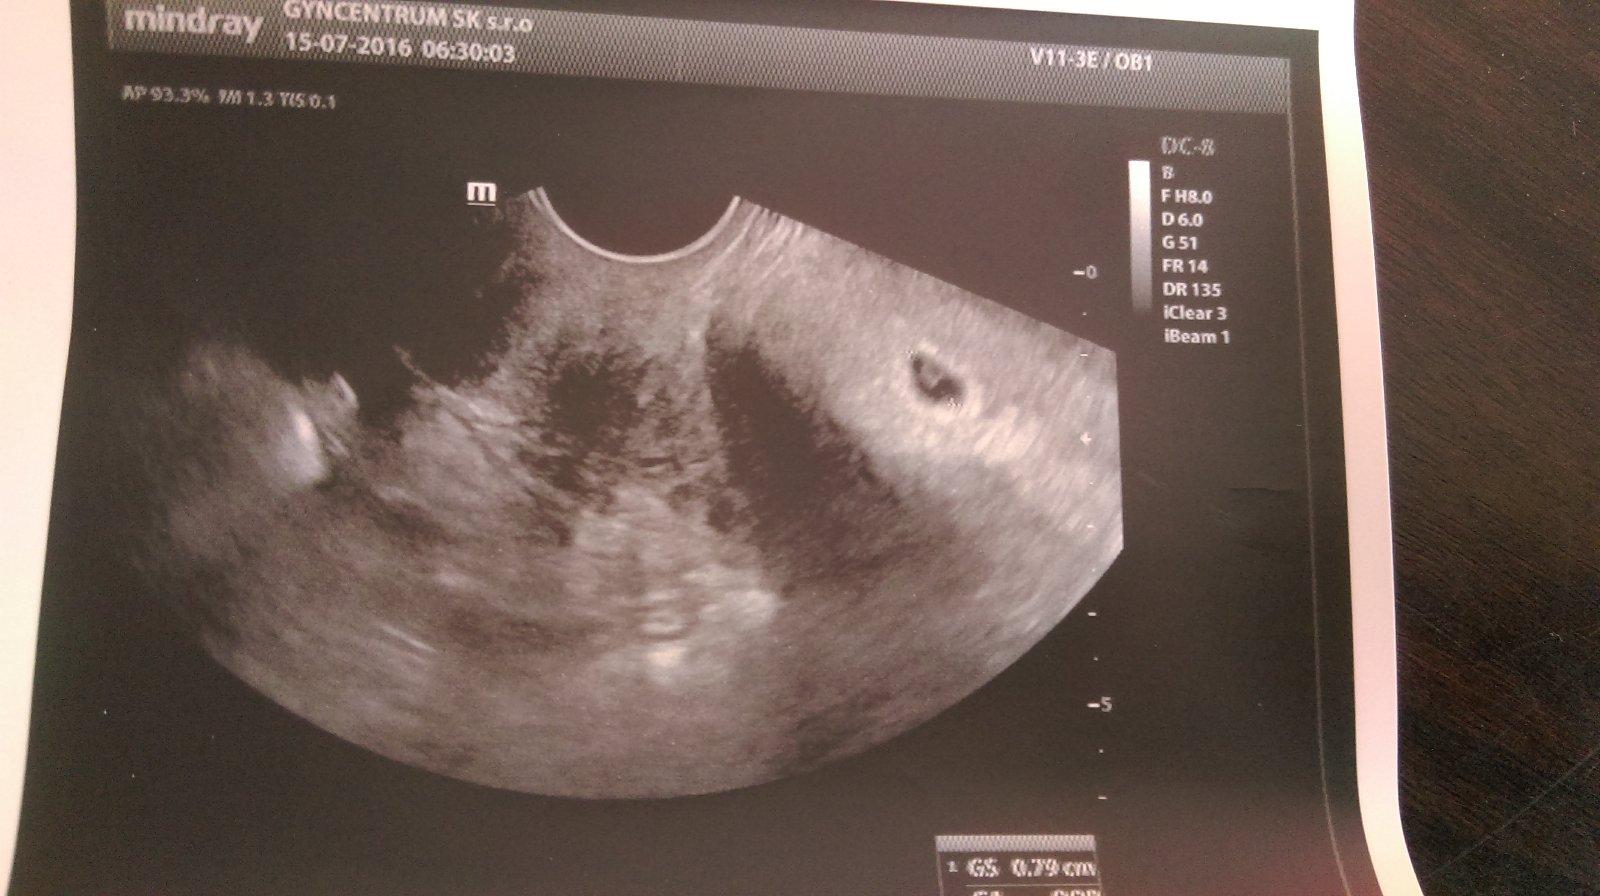

Urcite hned pisem ked budem vediet idem aj na sono aj ked neviem ci by bolo nieco vidno asi nie tak skoro 😉

@aluska1404 možno malinku gulicku gestacny vak bude vidieť ..drz sa a hneď daj vediet 😎

@14nunu10 To iz by mohlo ked bola vkadana blastocysta 6 dnova byt vidno???Asi hej lebo aj pri vklade mi dali obrazocok a tam bola gulocka malinka

@aluska1404 aj mne dali tu fotku pri vklade,ale keď som bola u gyndosa na 13 deň po ET bol vidieť gestacny vak pohladam foto